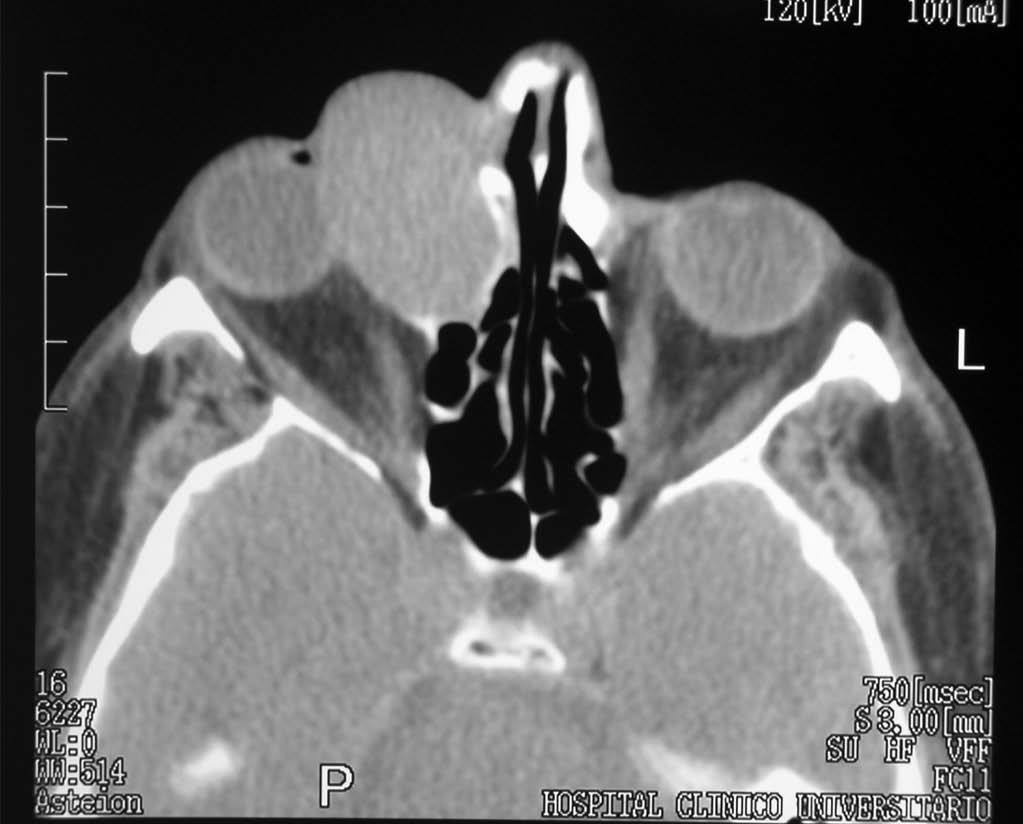

Se le realizó una TC orbitaria (figs. 1 y 2), sin administración de contraste intravenoso y se obtuvieron imágenes en los planos axial y coronal, con algoritmos de reconstrucción de partes blandas y de hueso. Se visualizaba la tumoración como una masa de partes blandas de densidad homogénea, morfología ovoidea, bordes bien definidos y contornos regulares, de 4 x 3 centímetros de diámetro anteroposterior y transversal respectivamente, localizada en el canto interno de la órbita derecha, que ocasionaba desplazamiento lateral del globo ocular y de la musculatura extrínseca ocular, con ensanchamiento del conducto lacrimonasal, que orientaba hacia un origen en el saco lacrimal. Se asociaba remodelación de las celdas etmoidales anteriores, sin evidenciarse signos de destrucción del hueso, ni afectación de estructuras vecinas.

Fig. 1.--Tomografía computarizada orbitaria, plano axial sin administración de contraste intravenoso. Se observa una masa de partes blandas bien definida, localizada en el canto interno de la órbita derecha, que produce el desplazamiento del globo ocular y musculatura extrínseca ocular y se asocia a ensanchamiento del conducto lacrimonasal.